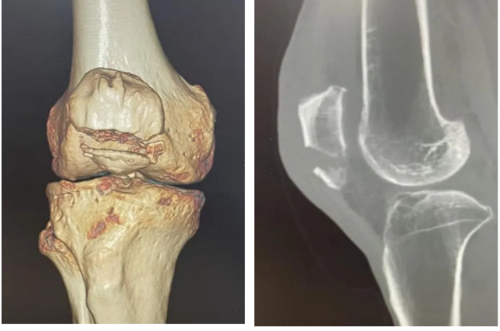

经充分论证与术前准备,手术如期进行,向飞帆博士与杨伟主任医师同台协作,过程规范精准。术后复查X片显示,张大爷骨折解剖复位,无金属内植物残留。“术后第二天我就能放心弯腿锻炼,换以前做手术哪能恢复这么快、这么省心啊!真是太感谢向医生和骨科的医生护士了!”张大爷在病房里一边轻松活动膝关节,一边难掩激动。

捕获1.PNG

▲术后复查X片示髌骨下极骨折解剖复位,无金属内植物